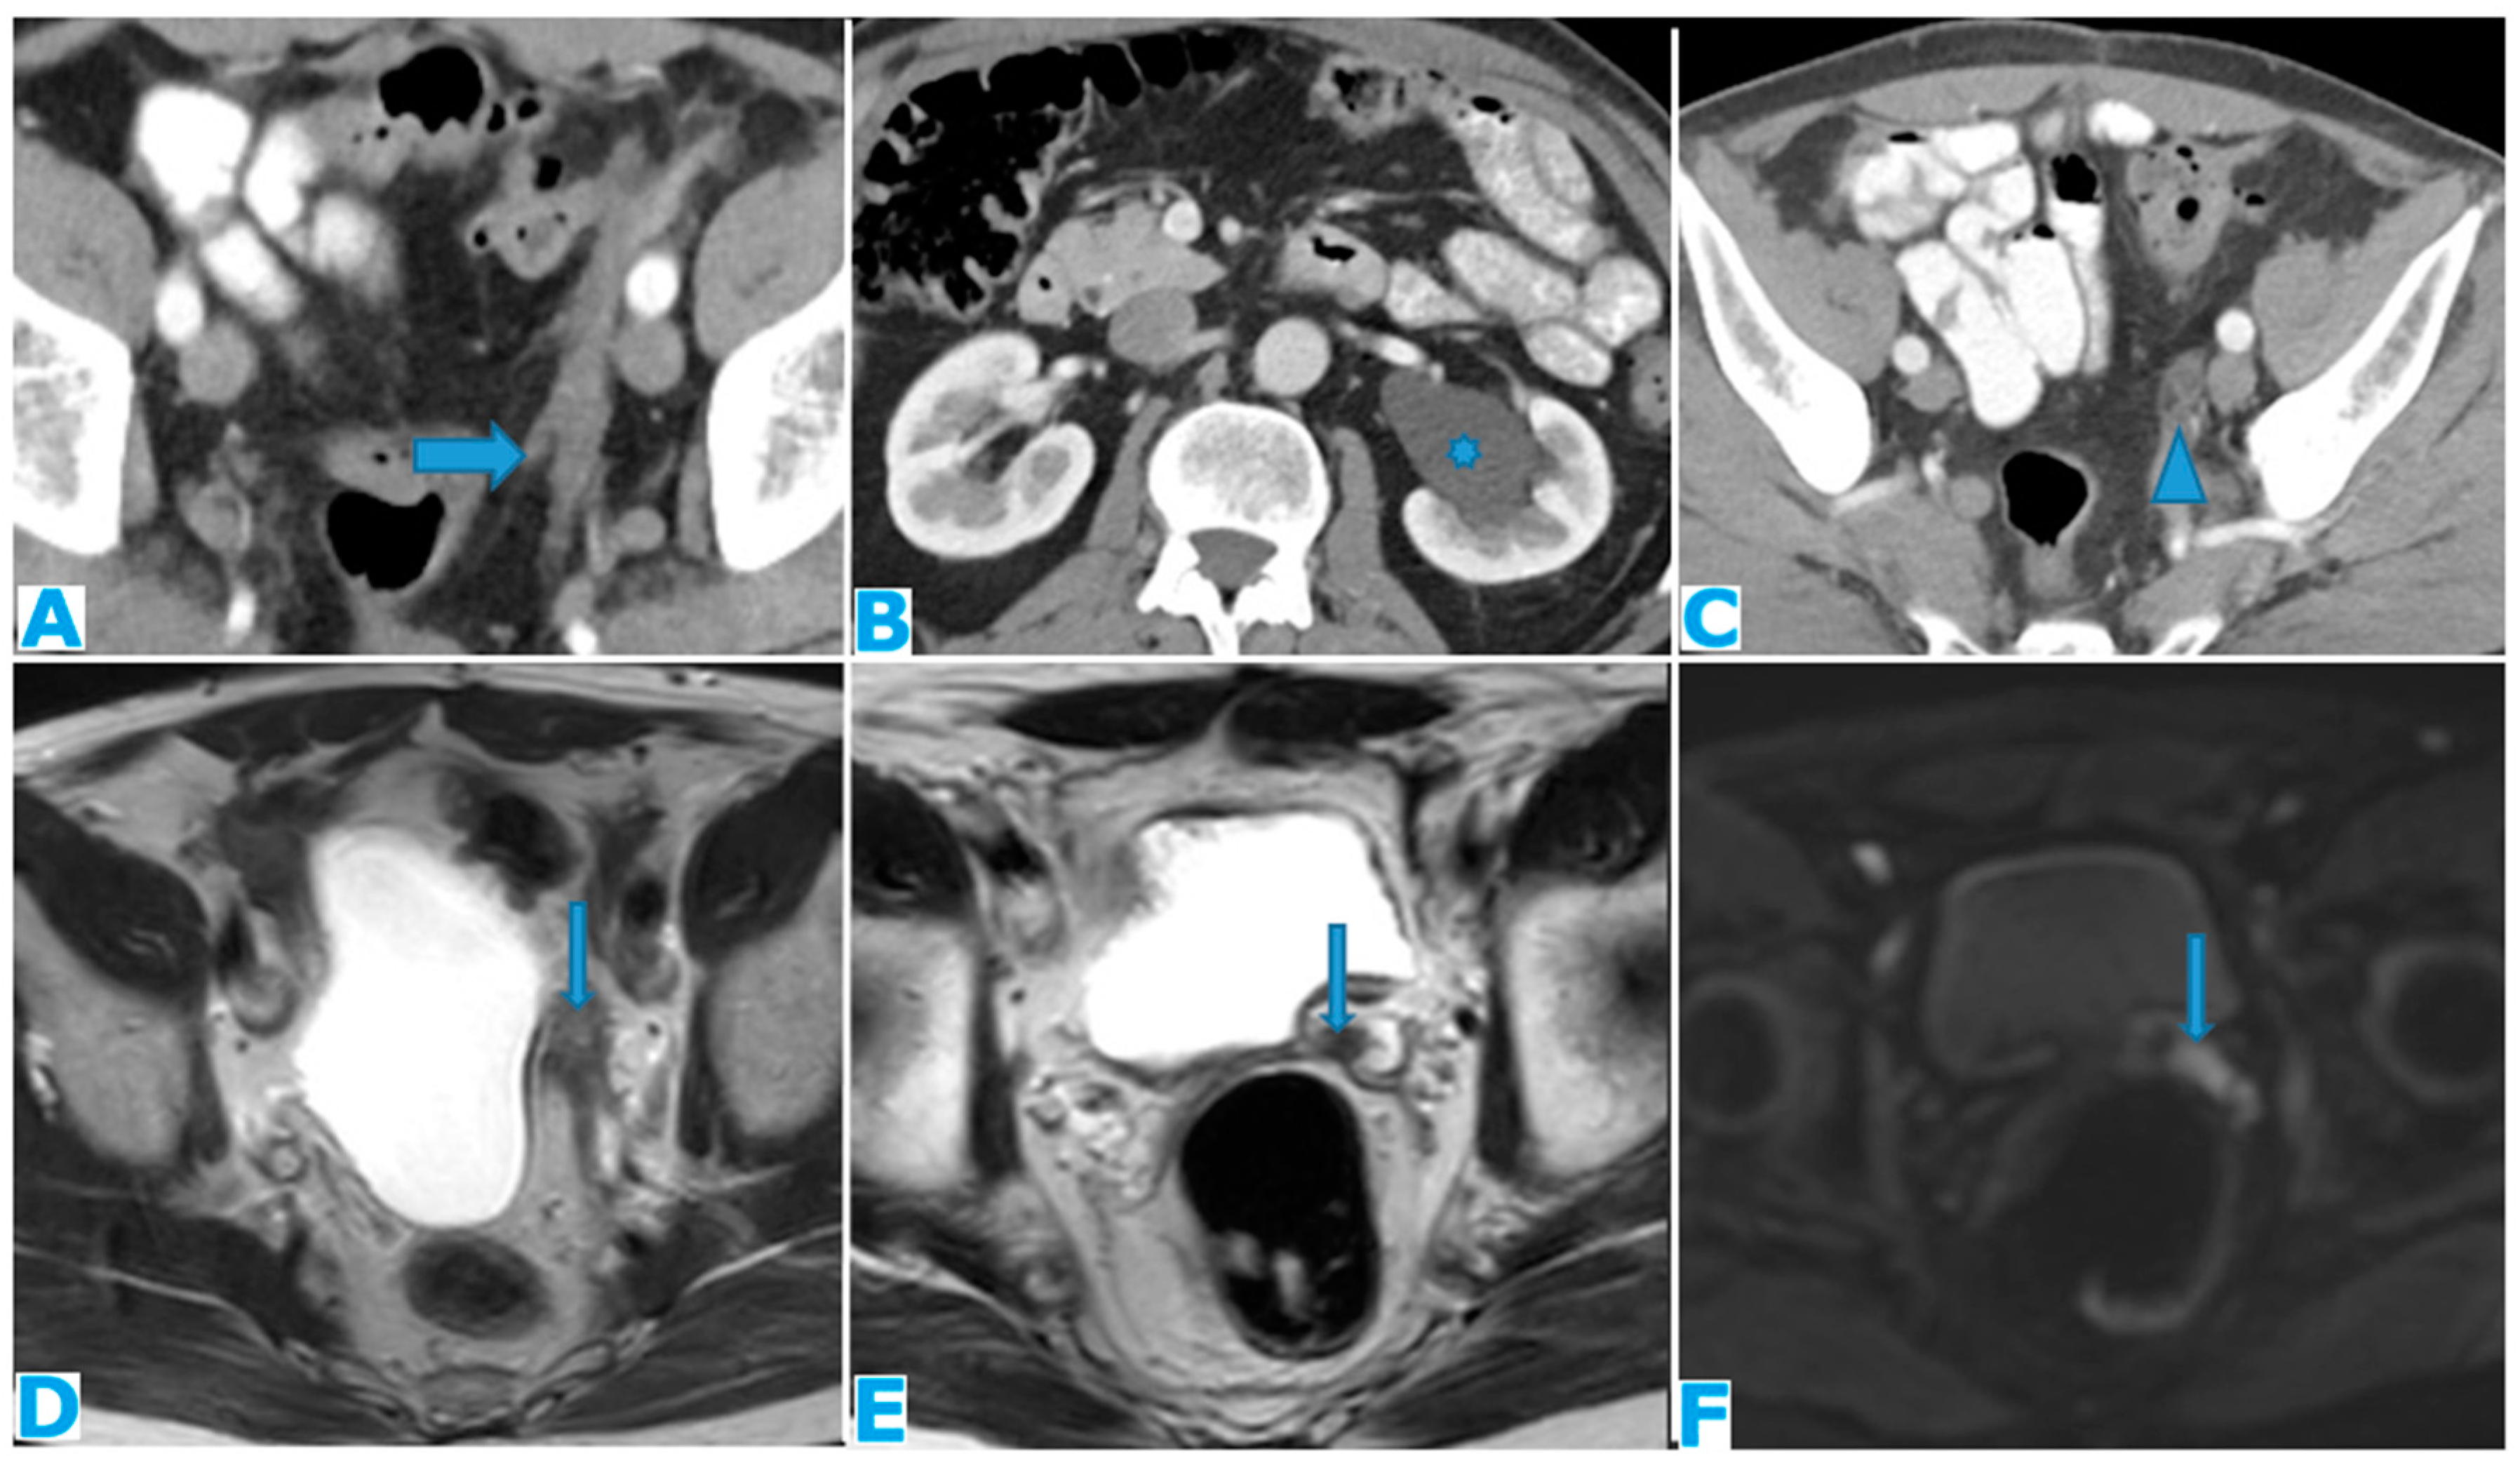

Figure 35.

Axial CE-CT (A, B, C). Axial T2WI (D and E), DWI (F). PC from mucinous adenocarcinoma of the appendix: Notice the peritoneal deposit within the left lateral pelvis (arrow on A) as an elongated soft tissue mass. The patient presented with a left uretero-hydronephrosis (* on B) due to the pelvic deposit which obstructed the ureter (arrowhead on C). Paravesical spaces are peritoneal recesses that cover on each side the distal ureter, the seminal vesicle, and the deferent duct. Note the deposit within the left paravesical space and how it obstructs the left ureter (arrow on C). The deposit also follows the course of the left deferent duct (arrow on E and F).